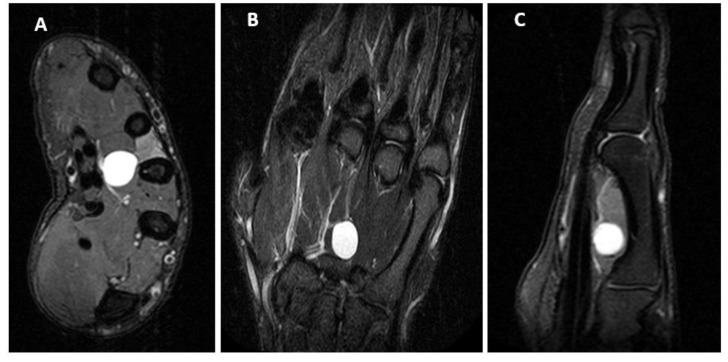

尺神经压迫常见于肘管处的肘部和盖恩管处的腕部,但很少见于手部。本病例报告描述了一名18岁男性,表现为7个月的非创伤性手部无力和与举重相关的萎缩。检查显示孤立性骨间肌萎缩,小指外展肌感觉完整,神经压迫试验呈阴性,包括腕和尺侧隧道的Tinel、Froment征、Wartenberg试验、交叉指试验和Spurling试验。肌电图和神经传导研究显示远端潜伏期延长,低振幅电位和大振幅纤颤,伴有第一背骨间肌运动单元放电严重减少,与尺神经深运动分支受损一致。磁共振成像显示一个神经节囊肿之间的第三掌骨轴和屈深肌腱。鉴于症状进展,行神经节囊肿切除及尺运动神经支松解术。

Ulnar nerve compression is commonly seen at the elbow at the cubital tunnel and the wrist at the Guyon canal but is rarely seen in the hand. This case report describes an 18-year-old male presenting with seven months of atraumatic hand weakness and atrophy associated with heavy weightlifting. Exam demonstrated isolated interosseous muscle atrophy mostly sparing the abductor digiti minimi with intact sensation and negative nerve compression tests including Tinel at carpal and ulnar tunnels, Froment sign, Wartenberg test, cross finger test, and Spurling test. Electromyography and nerve conduction studies demonstrated prolonged distal latency, low amplitude potential, and large amplitude fibrillations with severely reduced motor unit firing in the first dorsal interosseous muscle consistent with ulnar nerve deep motor branch compromise. Magnetic resonance imaging revealed a ganglion cyst between the third metacarpal shaft and the flexor profundus tendon. Given the progressive symptoms, ganglion cyst excision and ulnar motor nerve branch neurolysis were performed.